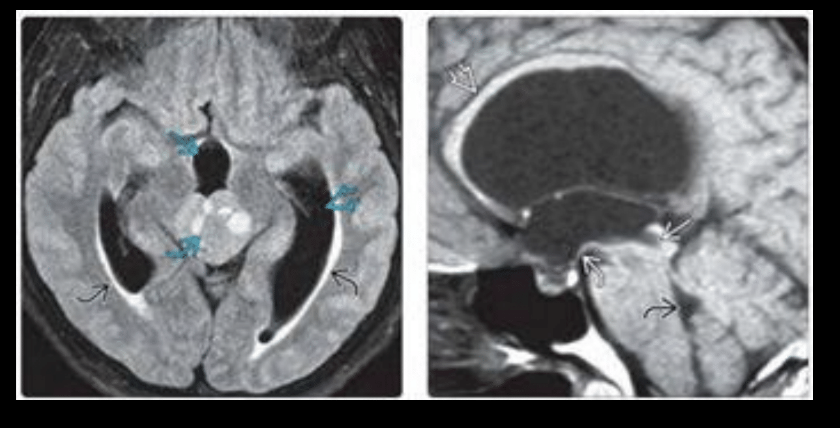

Patología de hidrocefalia extraventricular

Hemorragia: fibrosis: obstrucción ESA